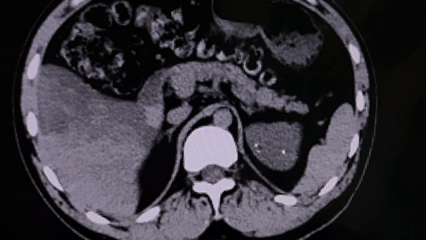

据了解,该患者因“左侧腰部间断性疼痛2月”来院就诊。经详细检查,诊断为左肾结石伴有积水和感染,且结石体积较大,已对肾功能造成潜在威胁,手术指征明确。同时,患者还合并双侧肾囊肿、髓质海绵肾及乙型病毒性肝炎,多重基础疾病为手术治疗带来了诸多挑战。

髓质海绵肾是一种先天性肾脏发育异常,患者肾集合管呈囊状扩张,易形成结石并反复感染,手术操作空间受限、出血风险较高;而乙型病毒性肝炎则对术中感染控制及术后康复管理提出了更高要求。面对复杂病情,泌尿外科团队高度重视,术前组织多学科会诊,围绕手术方式、围手术期感染防控、出血风险控制及肝功能保护等关键环节进行了充分评估与周密准备。